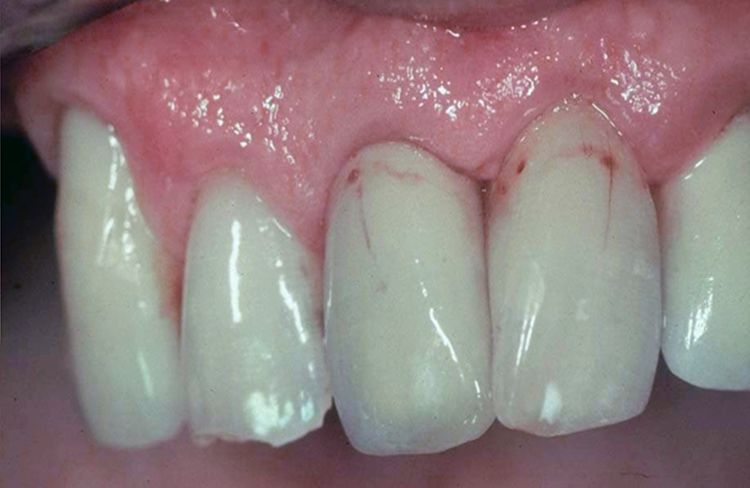

Implants vs. Dental Bridges

• Natural Replacement: Implants provide a more natural and cost-effective solution compared to bridges, which involve altering healthy teeth.

• Longevity: While bridges may last 5-10 years, implants offer a lifetime of functionality and durability.

(13 years After Placement)

“Dental implants prevent bone loss and preserve jaw strength and aesthetics.”

“Dental bridges risk gum disease, jaw shrinkage, and aging effects like wrinkles and bridge loss.”